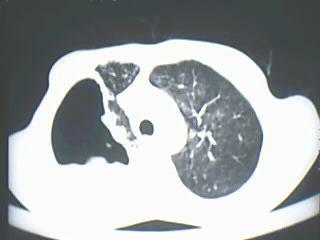

以下是引用随光逐影在2009-8-7 15:40:00的发言:[br]考虑右肺继发性肺结核并右肺上叶空洞形成,两肺支气管播散;不排除右肺上叶空洞内霉菌感染可能。

以下是引用jiangjing在2009-8-7 14:38:00的发言:[br]右上肺张力空洞,酐珞坏死灶,支气管扩张,多发播散灶,纵膈淋巴结显示,胸膜增厚---结核